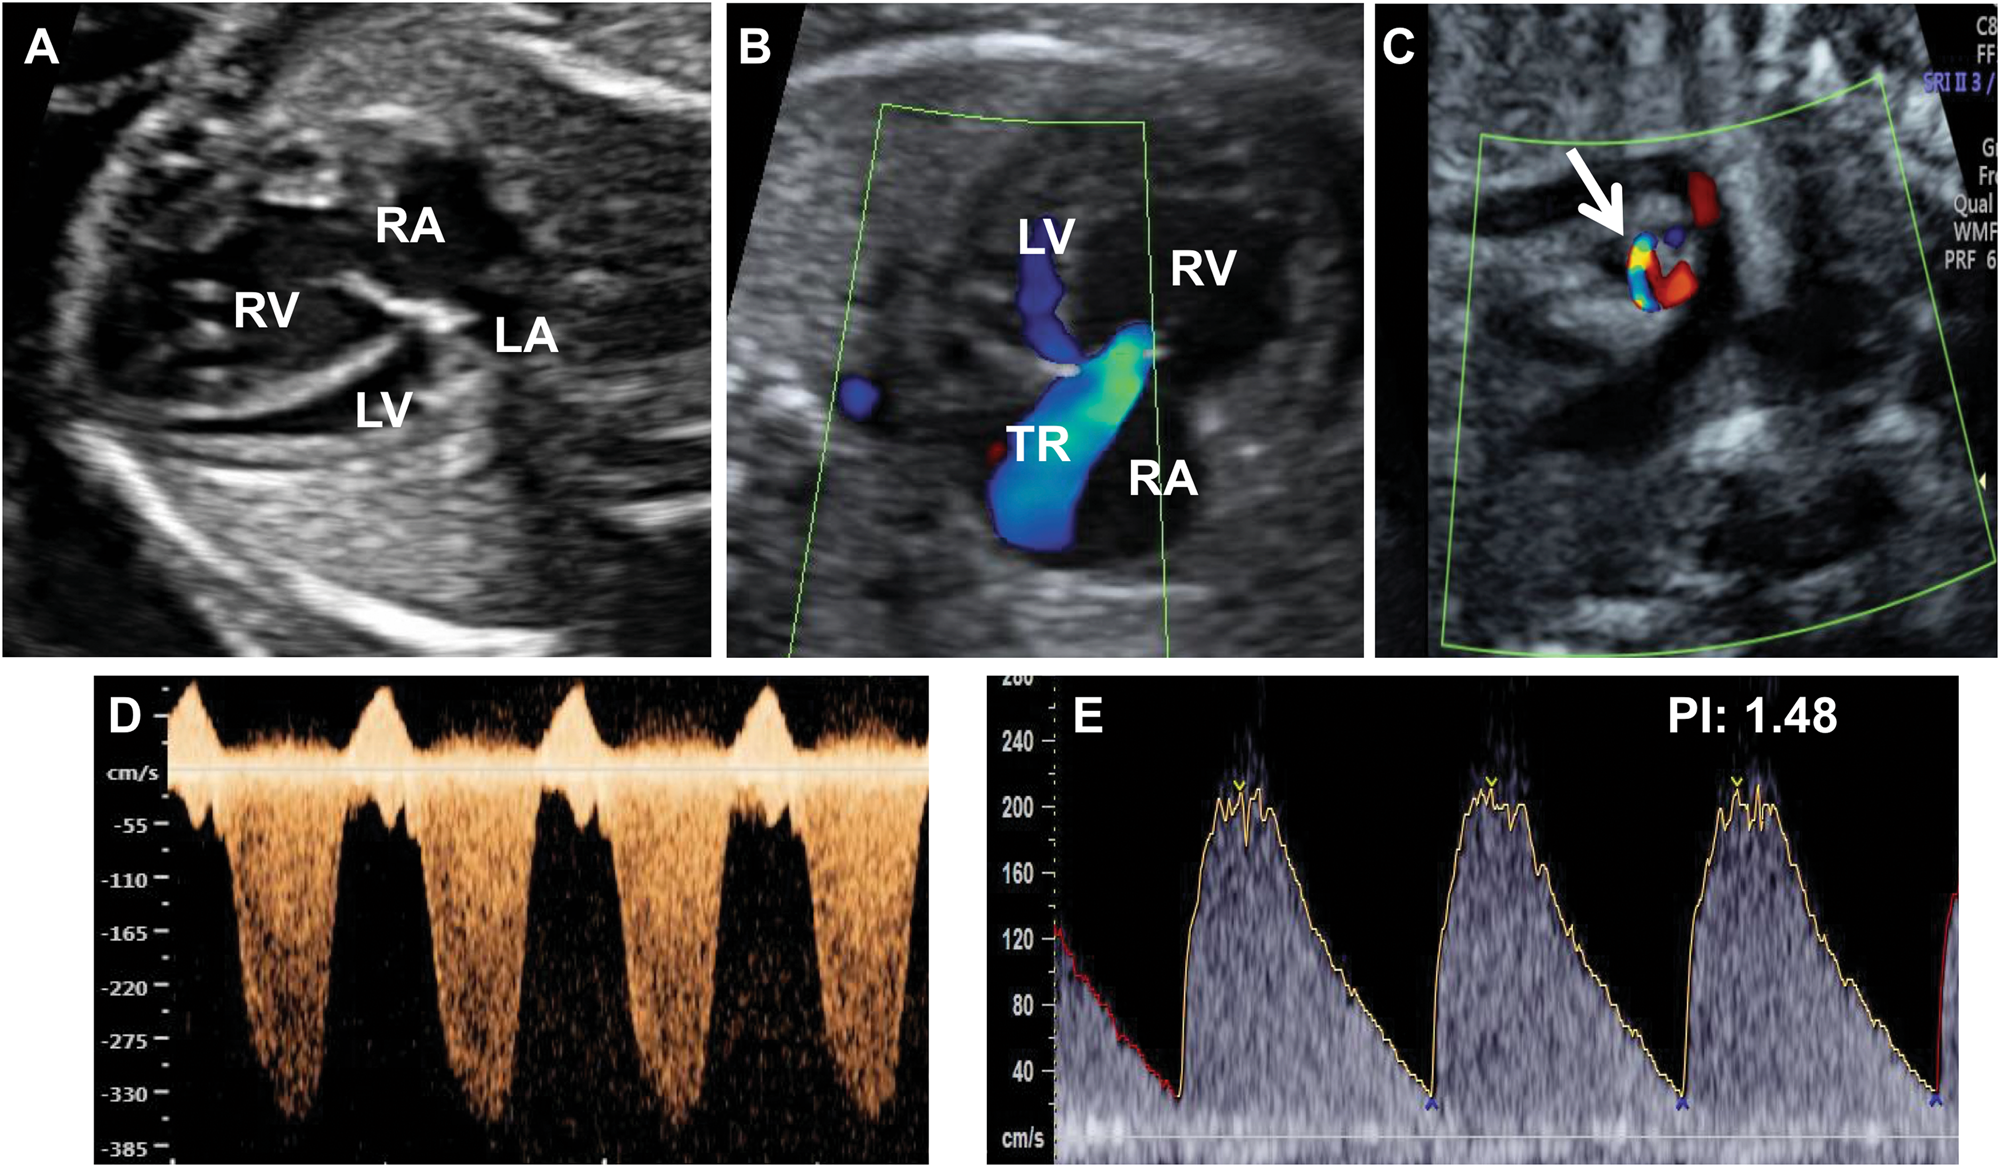

Antenatal closure of the ductus arteriosus and hydrops fetalis.

However the PDA in preterm infants is less responsive to this effect of oxygen and up. Older animal studies suggested a relationship between in utero exposure to NSAIDs in. Antenatal closure of the ductus arteriosus and hydrops fetalis.